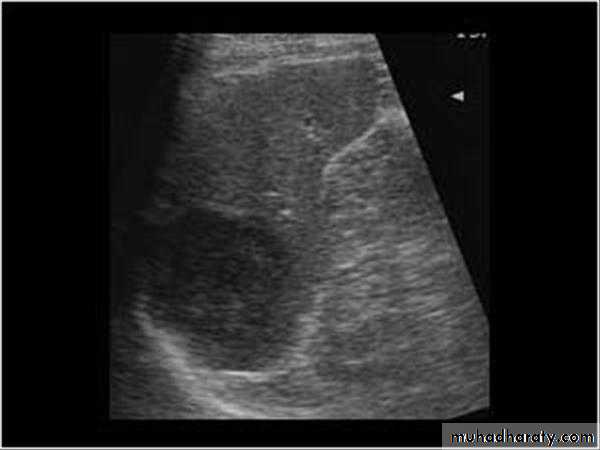

Malignant neoplasms:

hepatocellular carcinoma